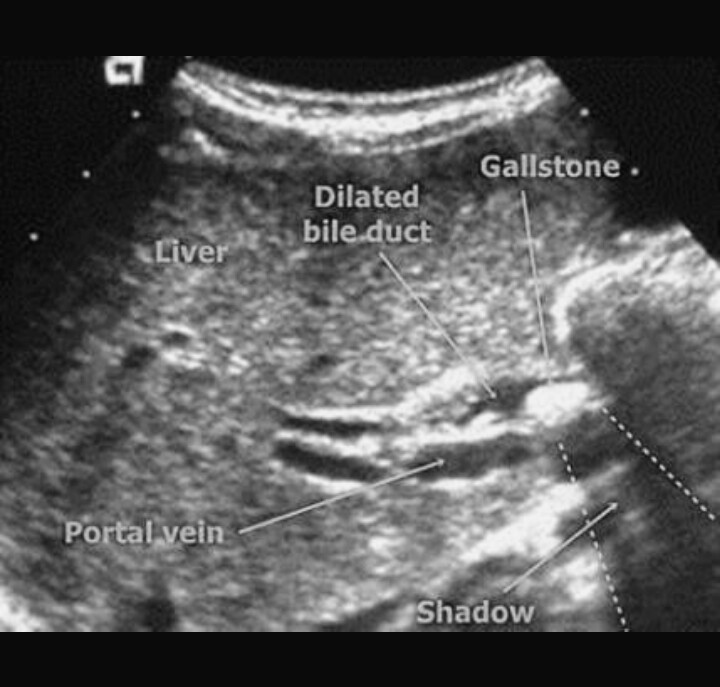

Define Medical Term Obstructive Jaundice . Also called obstructive jaundice, this type happens when a blockage stops bilirubin from draining into your bile ducts. Jaundice becomes visible when the bilirubin level is about 2 to 3. By sheila j toro, cc by 4.0, via wikimedia commons. Yellowish pigmentation of the sclera. Jaundice is a yellowish discoloration of the skin and mucous membranes caused by hyperbilirubinemia. Conditions that cause jaundice include: Obstructive jaundice, also known as cholestatic jaundice, is a condition characterized by the obstruction of bile flow from the liver to the. This condition is when bile isn't able to drain into your intestines because of a blocked or narrow bile or pancreatic duct.